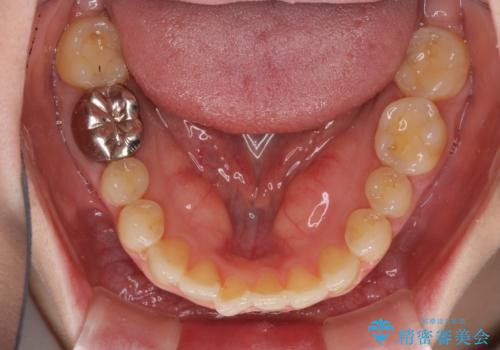

- 前歯のデコボコを治したいとのことで来院された患者様です。

上下顎ともに歯列全体の後方移動とIPR(歯と歯の間を削る)によってデコボコが解消するように設計し、インビザラインにより治療を行うこととしました。

1日22時間の装着時間をほとんど達成することができず、治療には当初予定の2倍以上の期間を要することとなりました。